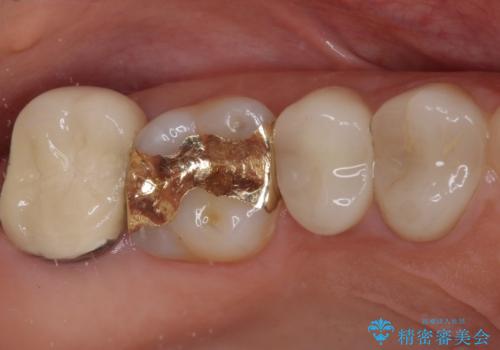

- 奥歯の間にものが挟まって不快であるとのことで来院された患者様です。

検査を行った結果、非常に強い咬合力により隣の歯との隣接面にひびが入り、虫歯が拡大している状態でした。

部分的にゴールドインレーが装着されていたので、虫歯と合わせて除去し、新たにゴールドインレーにて修復治療を行うこととしました。